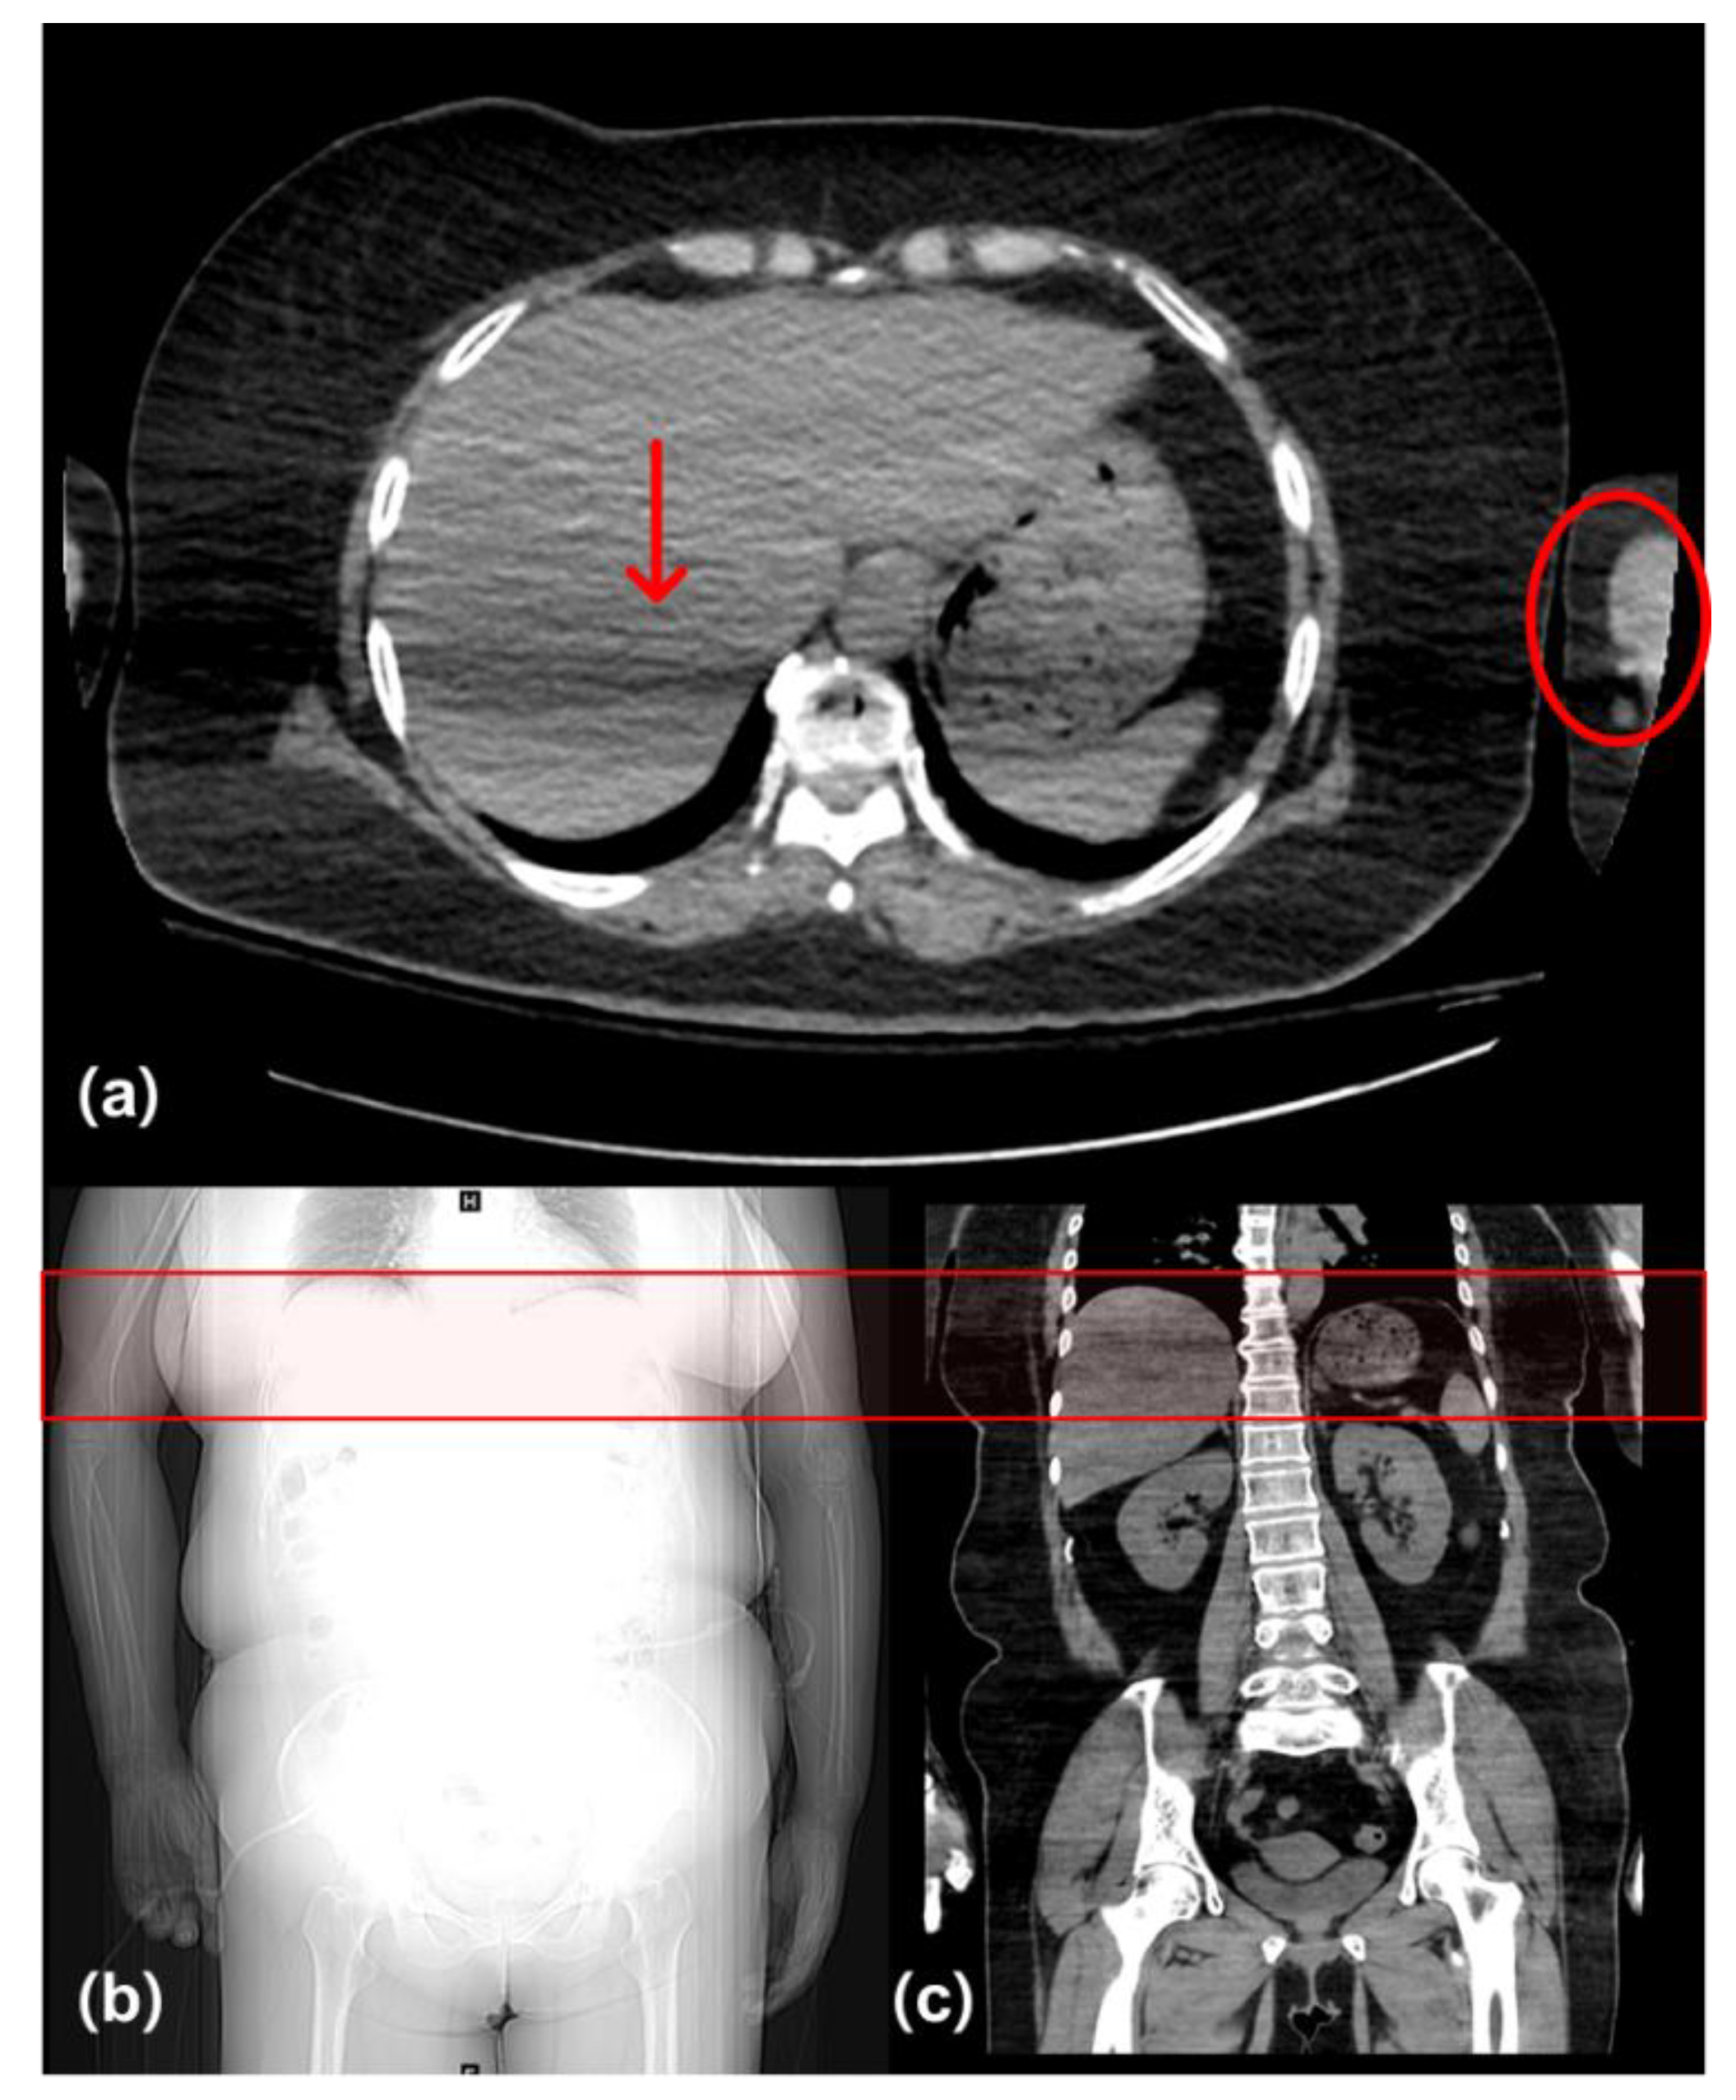

Figure 4. Abdominal CT images with an artifact (red arrow) due to overlap of the liver region with the distal humerus (red circle). This region has the greatest total effective thickness because of the arm (red box). (a) Axial image, (b) scout image, and (c) coronal image of a group A patient (M, 54 years, BMI: 31.87 kg/m2) with arms-down position. Values of CTDI and DLP were 9.60 mGy and 545.37 mGy·cm, respectively.

In a study of 177 patients conducted in 2008 [14], the CT images of patients with the arms-down position had lower image quality despite the high radiation dose. In this study, there was a difference in noise in the liver region between patients who had their arms down and those who had their arms raised. Kahn et al. [21] reported that artifacts caused by the arm interfered with the interpretation of liver hemorrhage. Another study reported that images of upper abdominal organ regions in patients with the arms-down position showed severe artifacts [15]. Since the liver region overlaps with the distal humerus, it has the greatest total effective thickness when the hand is lowered [22]. Therefore, the image noise is increased because of the reduced number of photons in the liver (Figure 4). The results of the quantitative evaluation in our study showed that the image noise in the liver region decreased in group B. Image noise can be lowered by increasing the tube voltage for photons that have been reduced due to the increased effective thickness. Further, there was no statistically significant difference in the mean values of groups A and B; however, differences in percentage according to the evaluation criteria were observed. In the four qualitative image evaluation criteria, group B received fewer scores of 2 or less and more scores of 3 or more than group A. The image in group B was not qualitatively inferior to that in group A. It was confirmed that the diagnostic acceptability for group A could be also maintained in group B, although it could not be concluded that the quality of the entire abdominal image in group B was improved than that of group A only by reducing liver region noise.